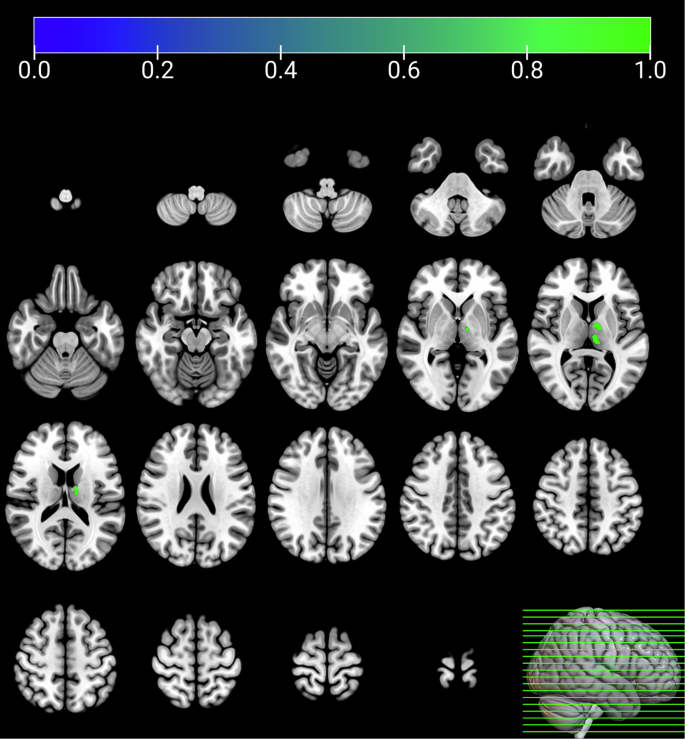

Group differences in GMV across the brain

After controlling for age, educational level, current smoking status, history of alcohol consumption, and TIV in the group comparison analyses, MUDs exhibited significantly reduced GMV in the left thalamus compared to HCs (cluster-wise p < 0.0001, FWE corrected; clusters size: 1771 mm3; Fig. 1). The mean GMV extracted from this cluster was significantly lower in the MUD group, with a moderate effect size (Cohen’s d = 0.44). No other brain regions exhibited significant group differences after correction for multiple comparisons.

HC vs. MUD; p < 0.0001, FWE corrected.